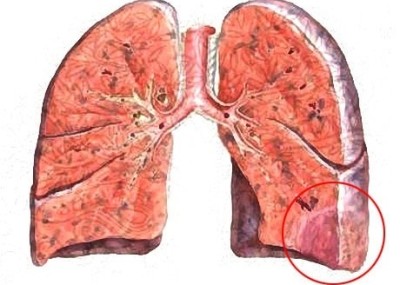

- инфаркт правого легкого наблюдается в 2 раза чаще, чем левого;

- нижние доли легких поражаются в 4 раза чаще, чем верхние.

Таким образом, наиболее часто подвергающаяся инфаркту локация – нижние доли правого легкого. Любая патология, развивающаяся в них (в частности, с выраженной симптоматикой ишемии тканей), должна каждый раз вызывать настороженность пульмонологов, не развился ли там инфаркт легкого.

В силу строения легкого его участок, пострадавший от нехватки кислорода, по форме похож на пирамиду (или клин). Ее верхушка направлена в сторону корня легкого, а основание – в противоположную сторону.

По мере того, как пораженная ткань страдает от нехватки кислорода, она становится темно-вишневого цвета, плотной по консистенции и выпирает над соседними здоровыми участками. Несмотря на то, что кровоснабжение плевры, прилегающей к пораженному фрагменту легкого, не страдает, она изменяется тоже – становится матовой, а дальше и вовсе тусклой, в соответствующем участке плевральной полости может накапливаться кровянистое содержимое.